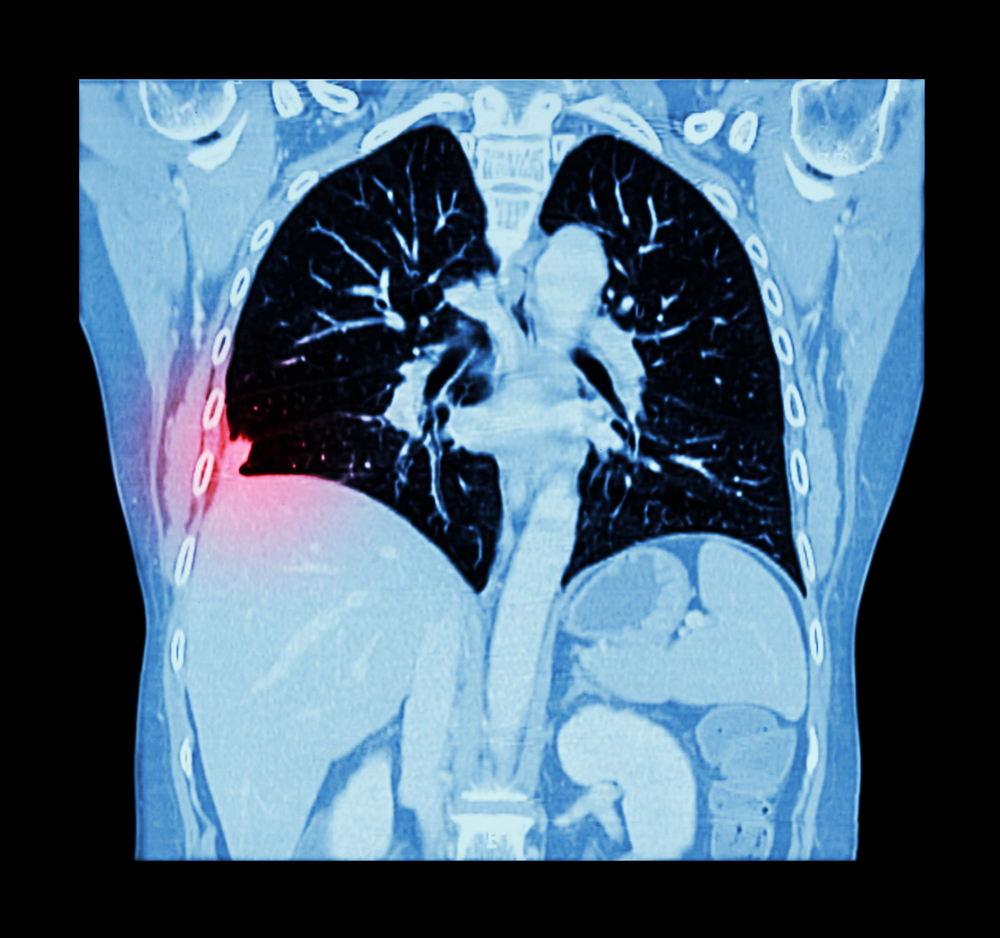

КТ легких и бронхов является одной из самых высокоинформативных диагностических процедур, которая позволяет получать послойные снимки органов грудной клетки и выявлять заболевания даже на самых ранних стадиях их развития. Получаемые после этого исследования рентгеновские снимки отображают все структурные изменения в тканях бронхов, легких, сосудов, трахеи и некоторых других органов. Для их получения используются рентгеновские лучи, но доза получаемого пациентом облучения намного ниже, чем при выполнении обычного рентгена. Несмотря на это, компьютерная томография (КТ) должна проводиться только по определенным показаниям.

При выполнении компьютерной томографии получается серия снимков, визуализирующих срезы находящихся в той или иной плоскости тканей. Это дает возможность оценивать плотность сегментов легких, выявлять присутствие гранулем (узелков) или новообразований, определять размеры патологических очагов и характеризовать качество кровообращения.

КТ-ангиография отображает сужение или расширение сосудов, нарушение их проходимости или присутствие жировых бляшек, тромбов или мальформаций. Этот режим томографии используется при диагностике опухолей для определения их четких границ, так как наличие этих образований нарушает кровообращение в тканях легких.